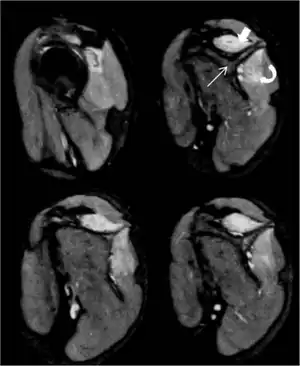

This syndrome can begin with severe shoulder or arm pain followed by weakness and numbness.[5] Those who suffer from Parsonage–Turner experience acute, sudden-onset pain radiating from the shoulder to the upper arm. Affected muscles become weak and atrophied, and in advanced cases, paralyzed. Occasionally, there will be no pain and just paralysis, and sometimes just pain, not ending in paralysis. MRI may assist in diagnosis.[7] Scapular winging is commonly seen.